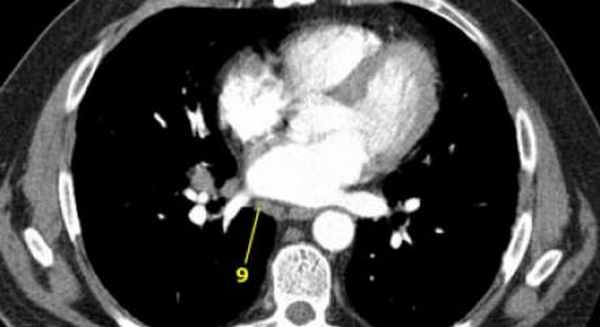

9. Узлы легочной связки. Лежат в пределах легочной связки.

9. лимфатические узлы легочной связки

Данные лимфатические узлы лежат в пределах легочной связки, в том числе и по ходу нижней легочной вены. Легочная связка представлена дупликатурой медиастинальной плевры охватывающей корень легкого.

9. Лимфатические узлы легочной связки: лежат в пределах легочной связки.